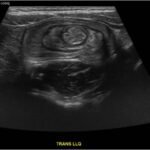

Intussusception is the telescoping of bowel into an adjacent segment of bowel and has an associated risk for bowel ischemia and perforation. The classic triad of abdominal pain, blood in stool, and an abdominal mass is present in less than 40% of pediatric cases and is less common in older children.1 Ultrasound has a high sensitivity and specificity for the diagnosis of intussusception, and once diagnosed, treatment modalities include reduction by either ultrasound or fluoroscopic guided air or hydrostatic enema. The risk of recurrence after successful reduction occurs in up to 12% of pediatric patients and occurs more frequently in older children and children with a pathologic lead point.2 We present a case of a 6-year-old child with colocolic intussusception that was successfully reduced and recurred within five days due to a large colonic polyp.